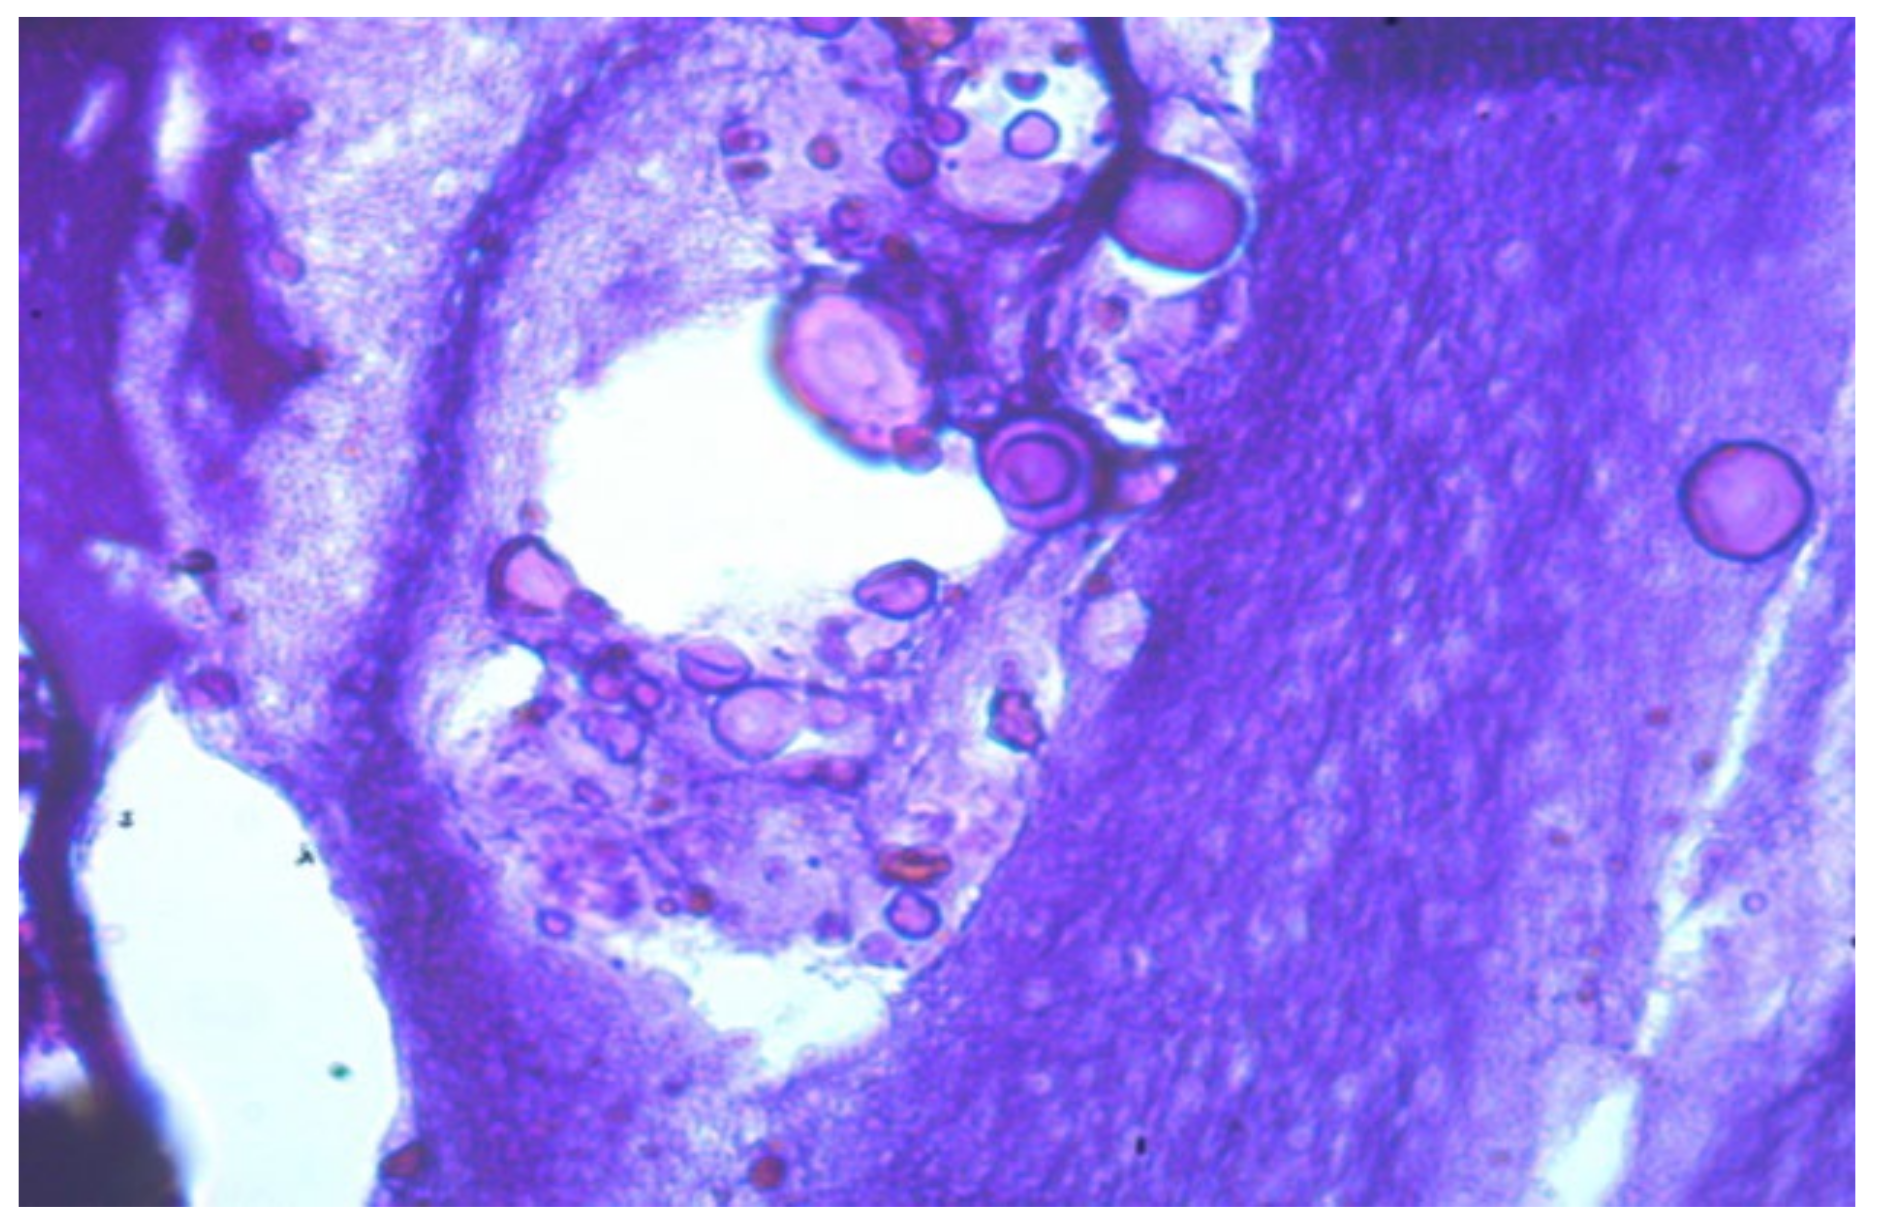

- Foreign substance (gel) migrated in the tissues, provoking the active growth of connective tissue;

- Aseptic and septic inflammatory reactions;

- Sections of round-shaped petrifications with clear contours;

- Lymphoid cell reaction, the presence of voids and necrotic masses, and the formation of cystic cavities;

- Pronounced deformation of adipocytes;

- Numerous mast cells;

- Isolated, giant Pirogov–Langhans cells surrounded by lymphocytes and macrophages.